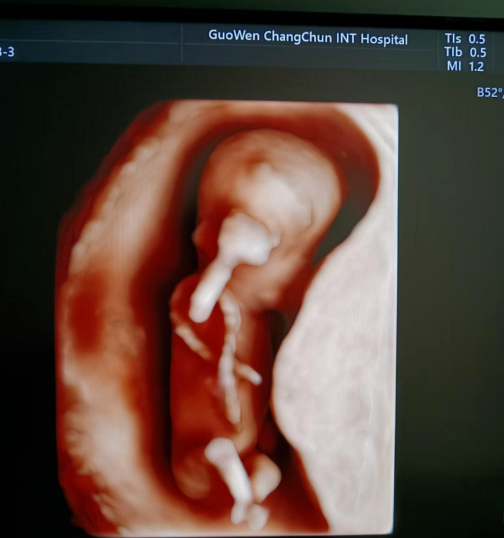

通常在懷孕 11 周 - 13 周 + 6 天之間進(jìn)行。這個(gè)時(shí)期胎兒大小適中,頸項(xiàng)透明層的顯示較為清晰,測(cè)量結(jié)果也相對(duì)準(zhǔn)確,能更好地發(fā)揮 NT 檢查對(duì)胎兒異常的篩查作用。

超聲檢查,孕婦無(wú)需空腹。檢查時(shí),超聲醫(yī)生會(huì)使用超聲儀器對(duì)胎兒頸部進(jìn)行仔細(xì)觀察和測(cè)量。通過(guò)超聲探頭可以清晰地看到胎兒在子宮內(nèi)的情況,重點(diǎn)測(cè)量胎兒頸項(xiàng)部皮下無(wú)回聲透明層最厚的部位,測(cè)量值即為 NT 值。正常胎兒 NT 值一般不超過(guò) 2.5mm。